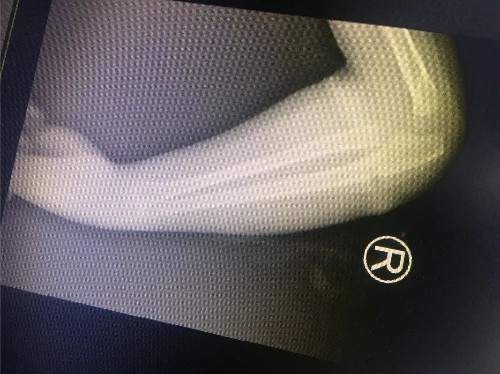

小孩5岁半 右胳膊肘处错位骨折 拍片后医生说